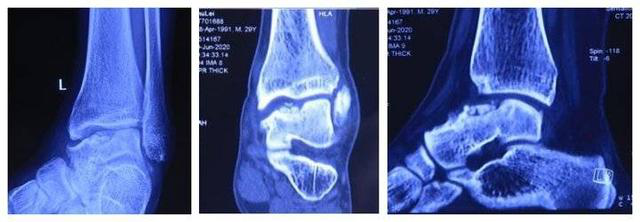

患者,男,28岁,左踝关节疼痛1年,加重3个月,影像学表现为左距骨内髁坏死、塌陷,面积约3*2cm大小。距骨坏死的治疗,对直径在2cm以内的距骨坏死,可以采用自体股骨髁骨软骨移植、自体带骨膜髂骨移植等方法,但对于直径超过2cm的距骨坏死,尤其是年轻患者,一直是治疗的难点。搜索国内外文献,对于超过2cm距骨坏死,一般采用踝关节融合、踝关节置换、同种异体距骨移植、全距骨置换等方法。但上述方法均有弊端:采用关节融合,患者丧失踝关节功能;踝关节置换、全距骨置换对于年轻、距骨单髁坏死患者,创伤大,且需要多次的返修手术;国外有采用同种异体新鲜距骨移植的报道,但目前国内还没有相关的骨组织工程库。经手术团队术前充分讨论,认为3D打印技术因其个性化的设计已经越来越多地应用于临床,决定对患者行3D打印距骨部分置换手术。